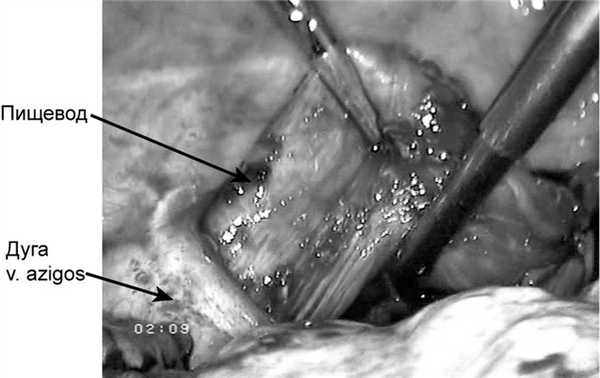

Предпочтение отдавали выполнению эзофагопластики целым желудком (39 человек). Первоначально формирование трансплантата производилось из лапаротомного доступа (45 больных). В последующем нами была разработана техника трансторакальной экстирпации пищевода из правостороннего доступа с одномоментной видеолапароскопической гастропластикой (11 человек). Учитывая трудности при выделении пищевода из рубцовых сращений и опасность повреждения прилежащих органов, производилось пересечение пищевода над дугой непарной вены с мобилизацией проксимального конца до верхней апертуры грудной клетки, а дистального - до диафрагмы (рис. 1).

Рис. 1. Выделение пищевода над дугой непарной вены.

Предпочтение отдавали эзофагопластике целым желудком (n=39). Первоначально трансплантат формировали, используя лапаротомный доступ (n=45). В последующем нами была разработана техника трансторакальной экстирпации пищевода из правостороннего доступа с одномоментной видеолапароскопической гастропластикой (n=11). Учитывая трудности при выделении пищевода из рубцовых сращений и опасность повреждения прилежащих органов, его пересекали над дугой непарной вены с мобилизацией проксимального конца до верхней апертуры грудной клетки, а дистального - до диафрагмы (рис. 1).

Рис. 1. Интраоперационная фотография. Выделение пищевода над дугой непарной вены.